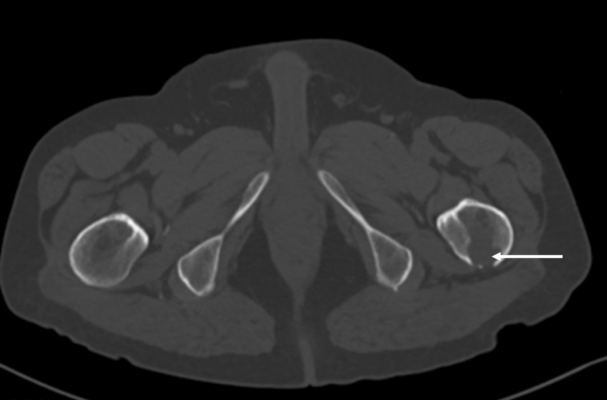

A hypodense region was noted in the left proximal femur on DXA image

A known lytic bone metastasis with cortical disruption seen on CT

For those patients with hypodense artifact identified in the hip, consider scanning the other hip or the forearm

Dual-energy X-ray absorptiometry (DXA) is the gold standard for measuring bone mineral density (BMD). While most exogenous materials (e.g., calcification, standard surgical hardware) present as hyperdense artifacts that falsely elevate BMD, certain high-density materials and lytic pathologies can manifest as “hypodense” artifacts (the “black hole” effect), leading to diagnostic challenges. A 47-year-old male with metastatic renal cell carcinoma (mRCC) on the tyrosine kinase inhibitor axitinib was referred for DXA following multiple atraumatic rib fractures. DXA imaging of the lumbar spine revealed a focal hypodense artifact over L1 (Fig 1A). Recent CT imaging for correlation identified this as a platinum-containing stent placed for a gastroduodenal artery aneurysm (Fig 1B). Consequently, L1 was excluded from the Z-score calculation to prevent inaccurate assessment. Additionally, a hypodense region was noted in the left proximal femur (Fig 2A), which matched a known lytic bone metastasis with cortical disruption previously seen on CT (Fig 2B). This case illustrates that high-atomic-number metals—such as platinum, tantalum, or lead—can paradoxicaly cause “black holes” on DXA because their extreme attenuation exceeds the software’s threshold for bone, causing it to incorrectly subtract the area as background or soft tissue. In this patient, the clinical picture was further complicated by lytic metastases from mRCC, which also produce focal hypodensity. Clinicians must maintain a high index of suspicion when encountering hypodense artifacts on DXA. Accurate interpretation requires correlation with anatomical imaging (such as radiographs, CT) and clinical history. Known causes of hypodense artifacts include lytic bone lesions, laminectomy sites, high-density metals (platinum, tantalum), and spina bifida.